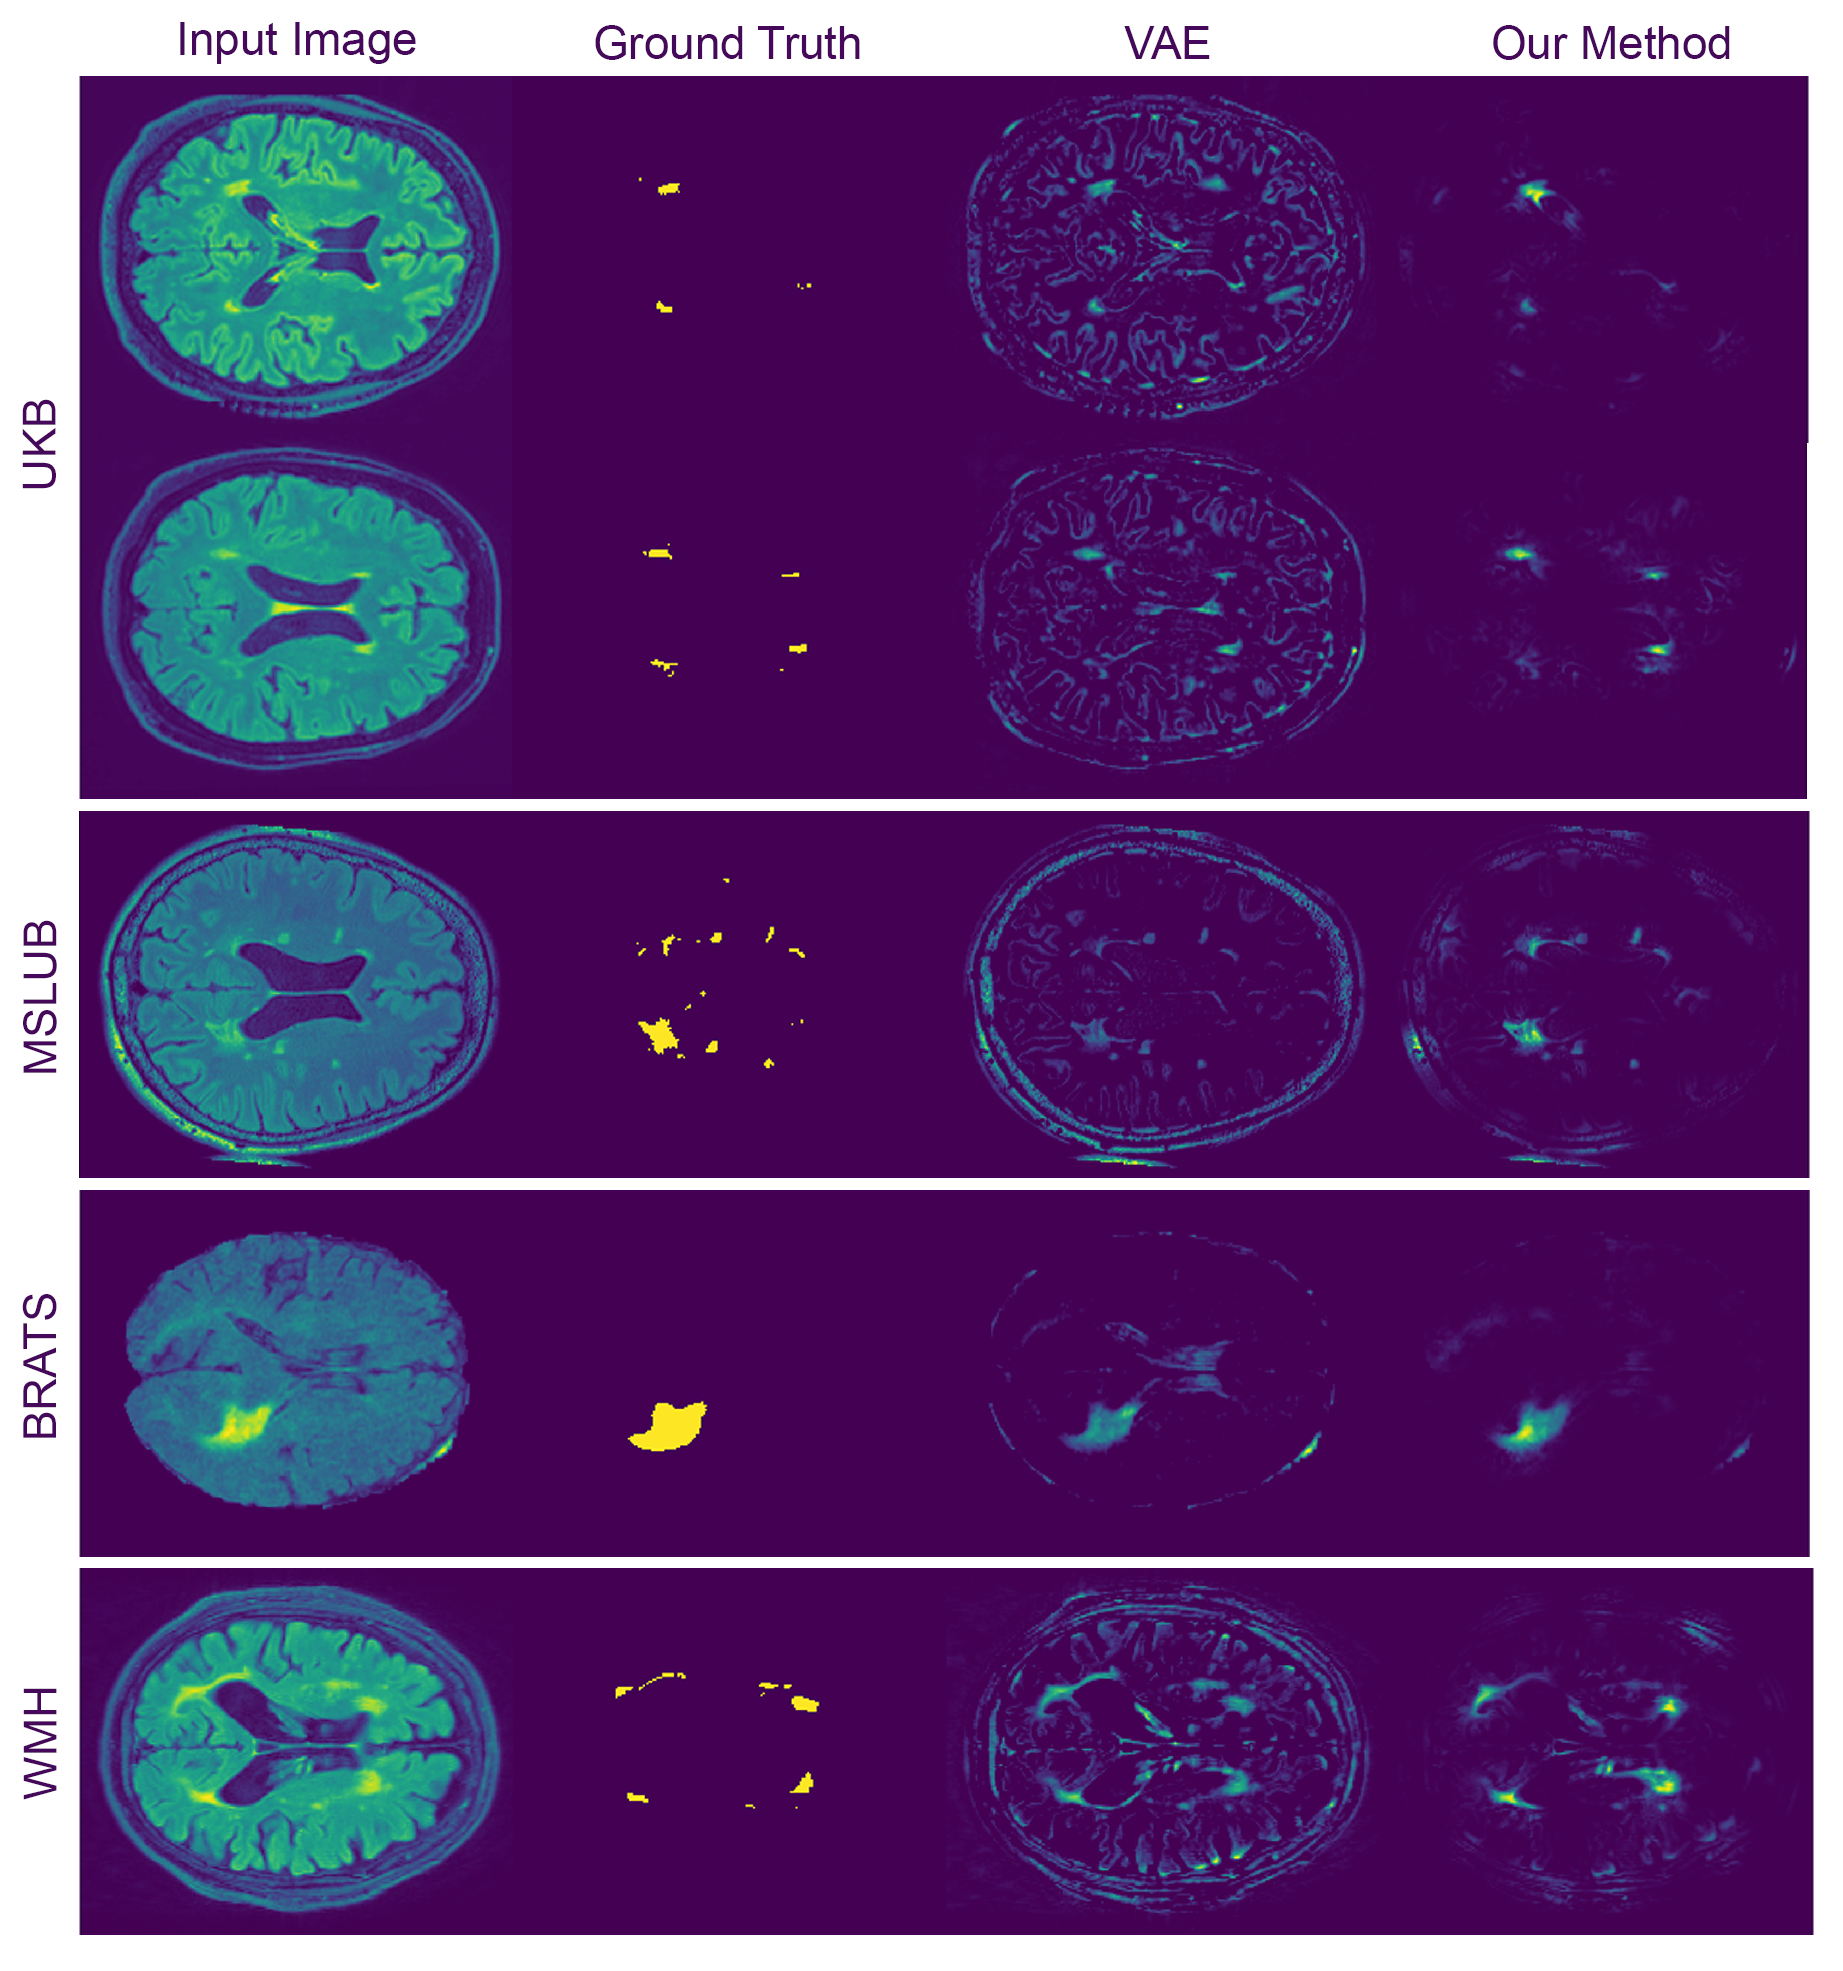

4.3 Experiment #3 – Anomaly Segmentation on Real Neuroimaging Data

To evaluate our method’s performance on real world lesion data, we used the FLAIR images from the UK Biobank (UKB) dataset Sudlow et al. (2015). We selected the 15,000 subjects, and their respective FLAIR images, with the lowest white matter hyperintensities volume, as provided by UKB, to train our models, as these subjects were the most radiologically normal. Then, we used 18,318 subjects from the remaining UKB dataset to evaluate our method to detect white matter hyperintensities (WMH).

In order to test for model generalisability, we also evaluated our method on three other datasets that also had FLAIR imaging data: the Multiple Sclerosis dataset from the University Hospital of Ljubljana (MSLUB) dataset Lesjak et al. (2018), which contains multiple sclerosis lesions; the White Matter Hyperintensities Segmentation Challenge (WMH) dataset Kuijf et al. (2019); and the Multimodal Brain Tumor Image Segmentation Benchmark (BRATS) dataset Bakas et al. (2017, 2018); Menze et al. (2014) that contain tumours (more information about the datasets and pre-processing on appendix A).

Our method showed a better performance than the autoencoder approaches from the literature in all datasets (\tablereftab:syntseg and Figure LABEL:fig:exp3). Compared to the numbers in Baur et al. (2020a), our autoencoder-based models got a lower performance on the common dataset (MSLUB dataset), where they achieved an DICE score of 0.271 with the AE (dense), 0.154 with the AE (spatial), and 0.323 with the VAE (dense). We believe that the discrepancy comes mostly from the significant post-processing of the Baur et al. (2020a) work as presented in Table 8 of this reference. Differences might also arise from the difference in resolution, as the DICE score is not invariant to resolution.